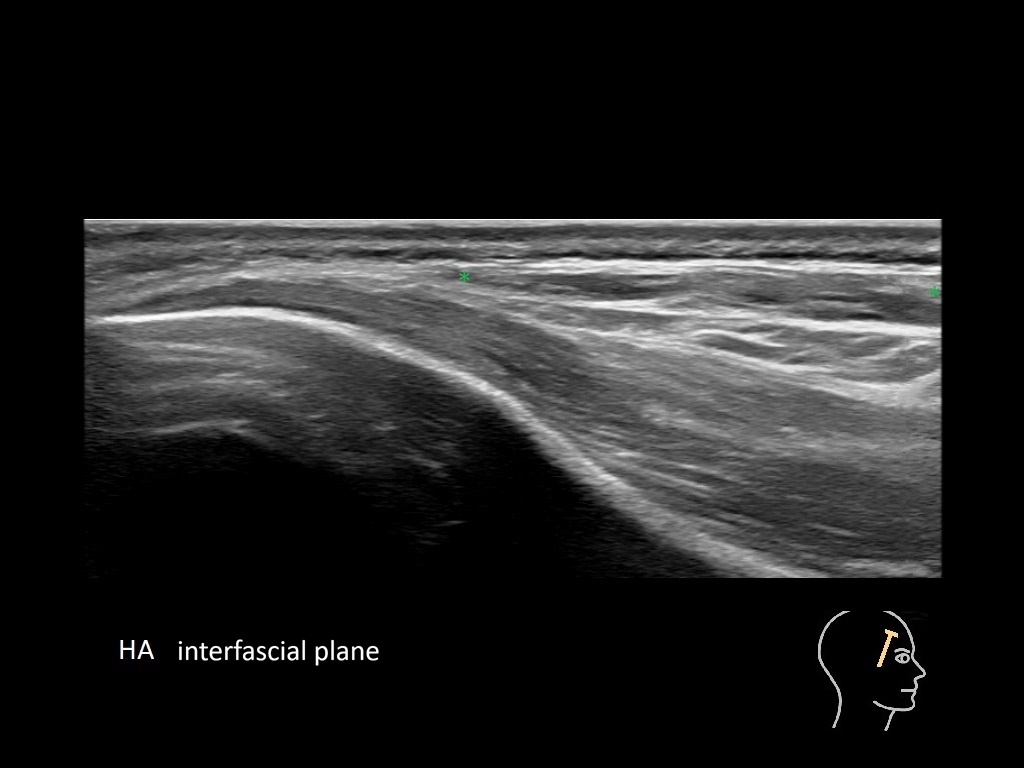

Draw in the second image below where the fillers are located. To check if your answer is correct, swipe the first image to the right.